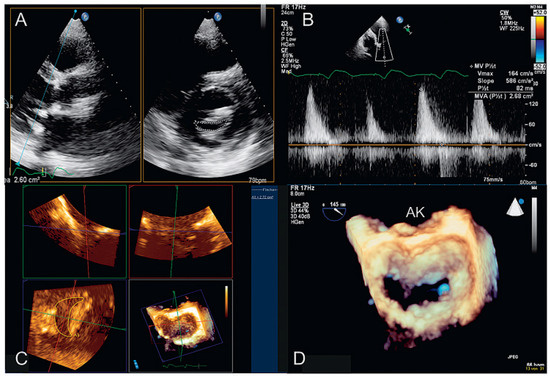

Dreidimensionale Echokardiographie zur Beurteilung der Mitralklappe

by Patric Biaggi, Christian Felix, Matthias Greutmann, David Hürlimann, Dominique Bettex and Felix C. Tanner

Using two-dimensional echocardiography, the complex anatomy of the mitral valve needs mental reconstruction into its three-dimensional shape. The power of both transthoracic and transesophageal three-dimensional echocardiography (3DE) lies in its possibility of showing the complex mitral valve anatomy in one single image, as [...] Read more.

Using two-dimensional echocardiography, the complex anatomy of the mitral valve needs mental reconstruction into its three-dimensional shape. The power of both transthoracic and transesophageal three-dimensional echocardiography (3DE) lies in its possibility of showing the complex mitral valve anatomy in one single image, as opposed to the mental reconstruction based on multiple two-dimensional images and schematic assumptions. Several 3DE modalities are used in daily life, including real time (“live”) modes as wells as postprocessed images. 3DE is of special interest in the evaluation of mitral stenosis, complex mitral valve prolapse and mitral valve prostheses. It has an established role in the perioperative mitral valve assessment during mitral valve surgery as well as during percutaneous mitral valve procedures. Limitations of 3DE are relatively low frame rates, an important learning curve as well as timeconsuming processing. Full article